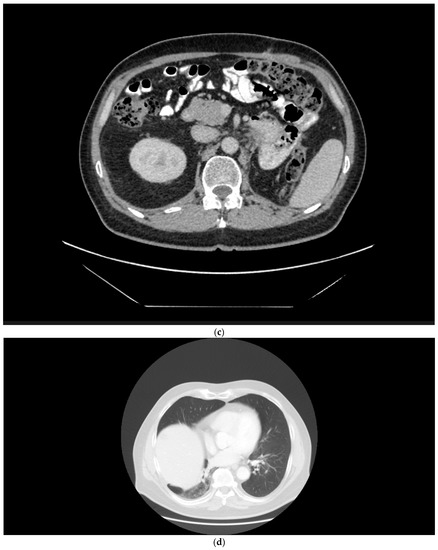

A 58-year-old male patient presented in November 2014 with a left renal mass and bulky retroperitoneal lymphadenopathy (Figure 2a). The patient had a short history of arterial hypertension and sinus tachycardia. Laboratory examinations at the time of diagnosis showed anemia, thrombocytosis, neutrophilia, and alanine aminotransferase (ALT) and aspartate aminotransferase (AST) CTCAE grade 1 elevation. The patient had the tumor removed in November 2014, but the surgery was only cytoreductive and not radical, leaving a left residual mass in the retroperitoneum. Histological examination revealed sRCC pT3pN1M0. A CT scan two months after surgery showed multiple lung metastases, 3 cm in size (Figure 2b), and a large mass in the retroperitoneum (Figure 2c). The patient had a poor prognosis score according to IMDC (anemia, neutrophilia, thrombocytosis, KPS, and interval to therapy initiation). The laboratory parameters of liver function improved after surgery and were within normal range. In March 2015, the patient was enrolled in the CheckMate 214 trial and received the combination therapy of nivolumab plus ipilimumab at a standard dose for four cycles, then continued with nivolumab monotherapy (3 mg/kg) every two weeks, achieving major partial response on CT examination within two months (Figure 2d). Soon after therapy initiation, the patient felt relieved, and his blood count was normalized. The patient continued with the therapy until October 2021, when the therapy was permanently stopped due to grade 3 ALT and AST elevation. Intravenous methylprednisone 1 mg/kg was immediately initiated. Liver tests gradually returned to normal, and all clinical symptoms accompanying the course of therapy that the patient did not consider, including grade 1 diarrhea, grade 2 insomnia, and grade 1 joint pain, disappeared. The patient continues to be followed. At the last visit in May 2022, he was without evidence of disease activity.

Figure 2.

(a) Patient 2, pretreatment CT of the renal tumor. (b) Patient 2, pretreatment CT of the chest demonstrating lung metastases. (c) Patient 2, a large mass in the retroperitoneum. (d) Patient 2, major partial response after the combination regimen of ipilimumab with nivolumab.